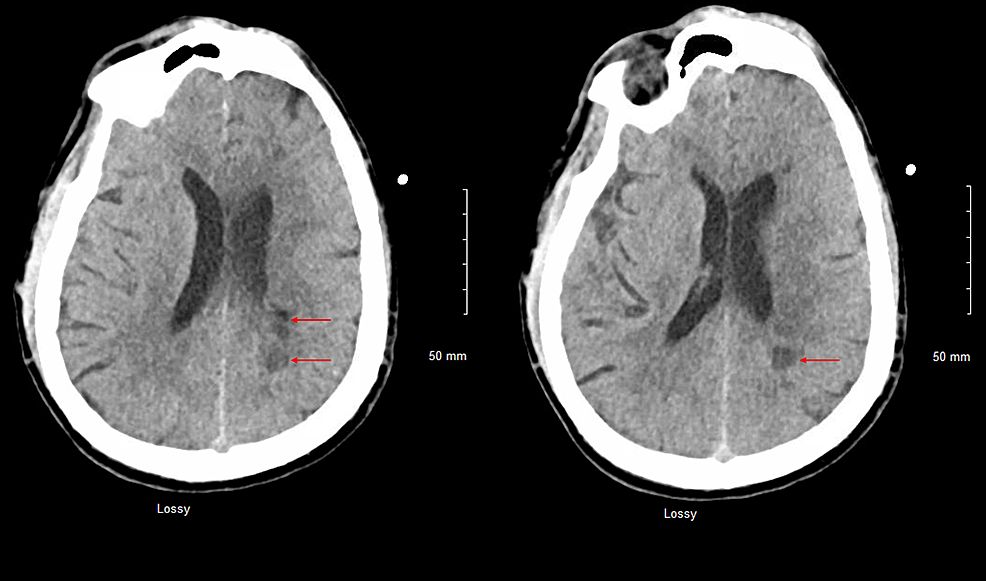

Repeat CT head, CTP of the head, and CTA of the head and neck revealed multiple white matter hypodensities concerning septic emboli, bilateral internal carotid artery 50% calcific stenosis, and no focal perfusion defects (Figure 2,3).

CT-head-axial-view-plain-revealed-multiple-white-matter-hypodensities-concerning-septic-emboli-(Red-arrows).

CT-head-sagittal-view-plain-revealed-multiple-white-matter-hypodensities-concerning-septic-emboli-(Red-arrows).